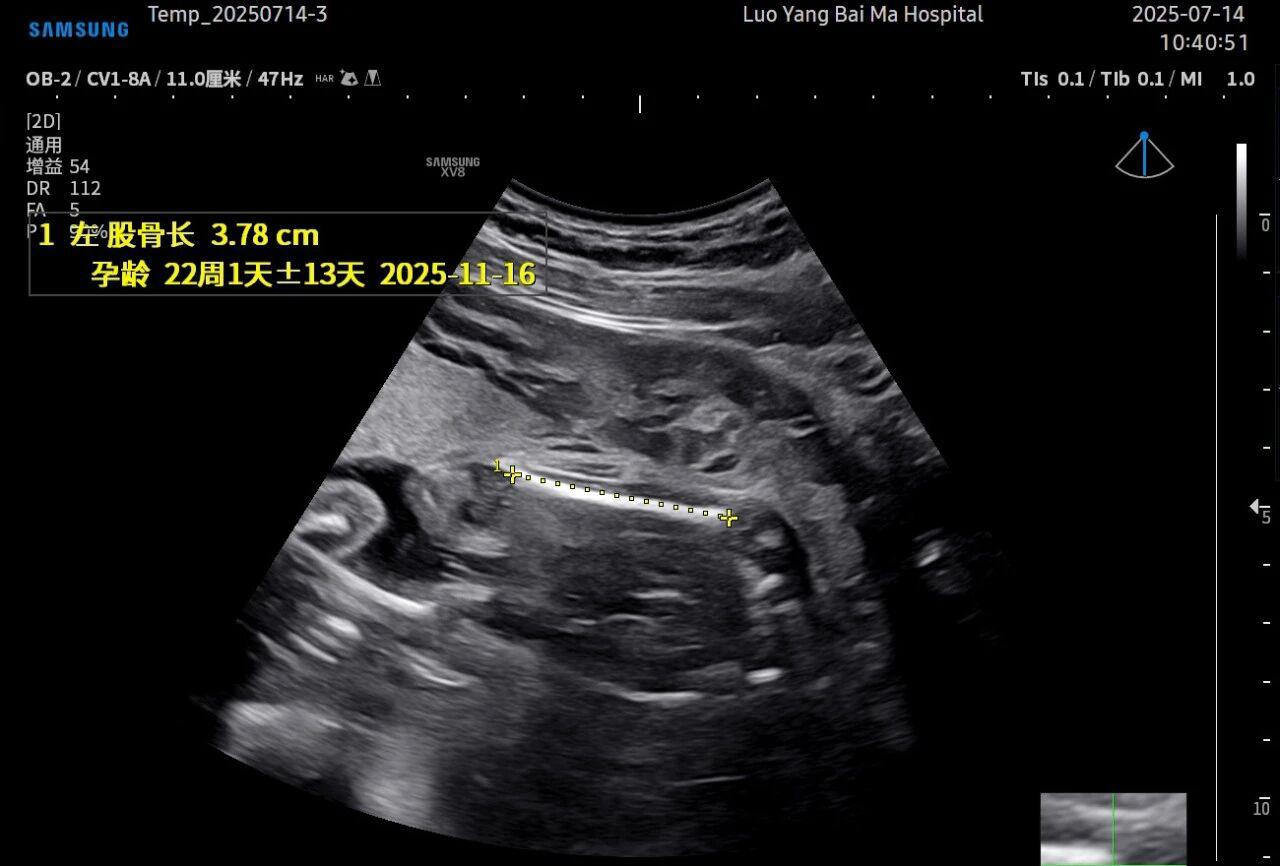

这是5D技术的核心优势之一。系统内置了强大的智能化大数据分析功能和AI辅助诊断工具。例如,在进行胎儿颈项透明层(NT)测量、胎儿长骨(LB)测量等关键生物学指标评估时,5D智能系统可以自动识别解剖层面、智能勾勒测量范围并进行计算。这不仅大大缩短了检查时间,更重要的是,它通过标准化的智能算法减少了因人为操作可能产生的误差,使诊断结果更加客观、可靠。

• 5D彩超检查通常建议在孕20-26周,尤其推荐在孕22-24周进行。此时胎儿大小适中,羊水量充足,图像清晰度较高。